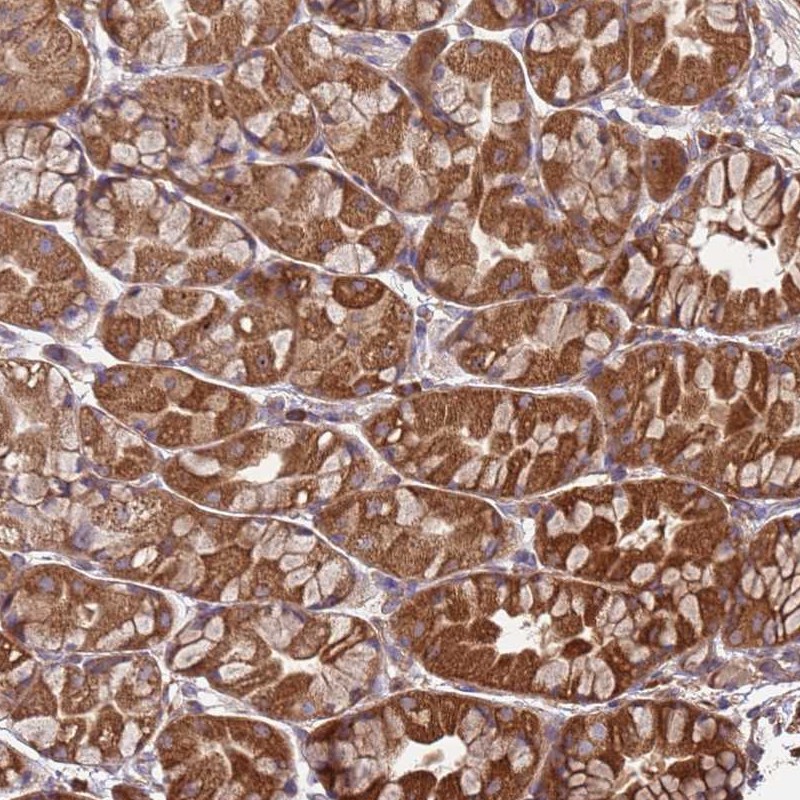

Immunohistochemical staining of human stomach, upper shows strong cytoplasmic positivity in glandular cells.